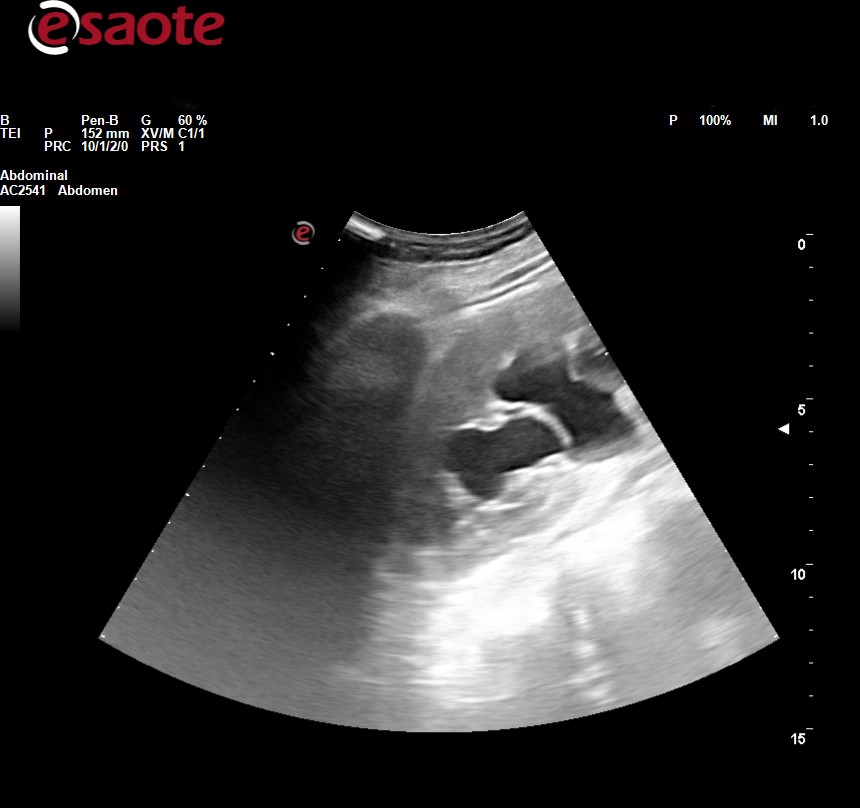

Ecografía clínica abdominal: observamos dilatación ureteropielocalicial bilateral junto con pared engrosada de la vejiga.

JC: hidronefrosis bilateral con engrosamiento de la pared vesical.

Se la deriva a urgencias hospitalarias, donde amplían estudio con analítica general (HB 9.1) bioquímica (creatinina 4.2, FG 11), urocultivo (negativo), p. de coagulación (normal), ecografía( obstrucción de vía urinaria bilateral asociada a engrosamiento mural vesical con signos de vejiga de lucha no se puede descartar malignidad), TAC abdominopélvico (riñón izdo atrófico, dilatación de la vía urinaria con aumento marcado y difuso de las paredes de la vejiga y formaciones diverticulares en ambas caras laterales), cistoscopia (vejiga de aspecto inflamatorio, engrosada, parcheada), biopsia (inflamación crónica) y pielografía descendente (permeabilidad de ambos uréteres con adecuado paso de contraste a vejiga)